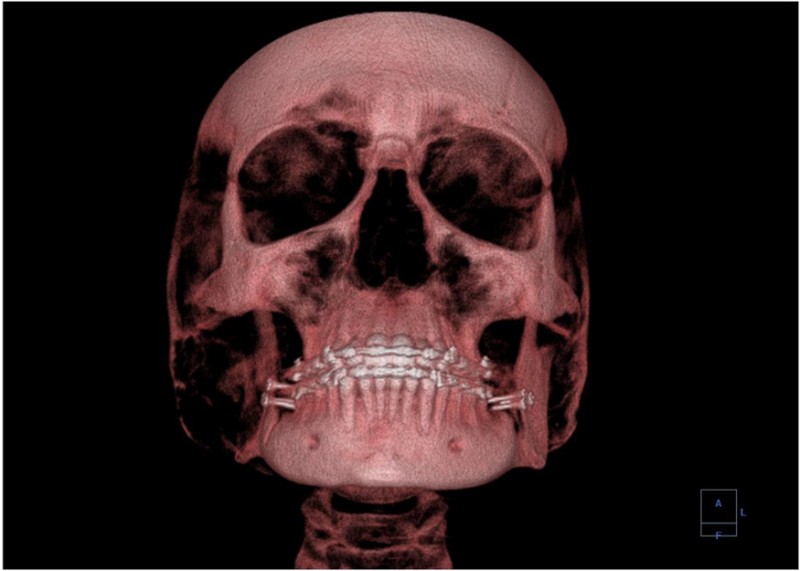

A standard x ray gives only a two-dimensional view of the object. Dense bones might hide images of soft tissue or organs. If you took another x ray from the side of the person (the first one being from the front), you would gain additional information. While shadow images are sufficient in many applications, far more sophisticated images can be produced with modern technology. This figure shows the use of a computed tomography (CT) scanner, also called computed axial tomography (CAT) scanner. X rays are passed through a narrow section (called a slice) of the patient’s body (or body part) over a range of directions.

An array of many detectors on the other side of the patient registers the x rays. The system is then rotated around the patient and another image is taken, and so on. The x-ray tube and detector array are mechanically attached and so rotate together. Complex computer image processing of the relative absorption of the x rays along different directions produces a highly-detailed image. Different slices are taken as the patient moves through the scanner on a table. Multiple images of different slices can also be computer analyzed to produce three-dimensional information, sometimes enhancing specific types of tissue, as shown in this figure. G. Hounsfield (UK) and A. Cormack (US) won the Nobel Prize in Medicine in 1979 for their development of computed tomography.